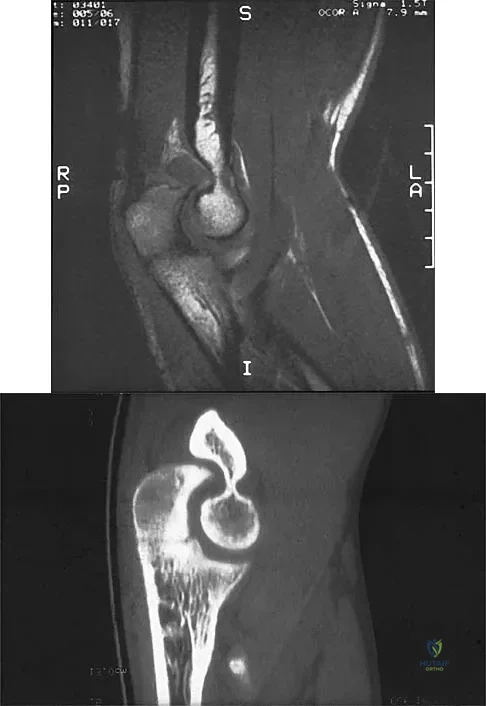

A 16-year-old girl has a painful foot mass. A radiograph, MRI scan, and biopsy specimens are shown in Figures 35a through 35d. What is the most likely diagnosis?